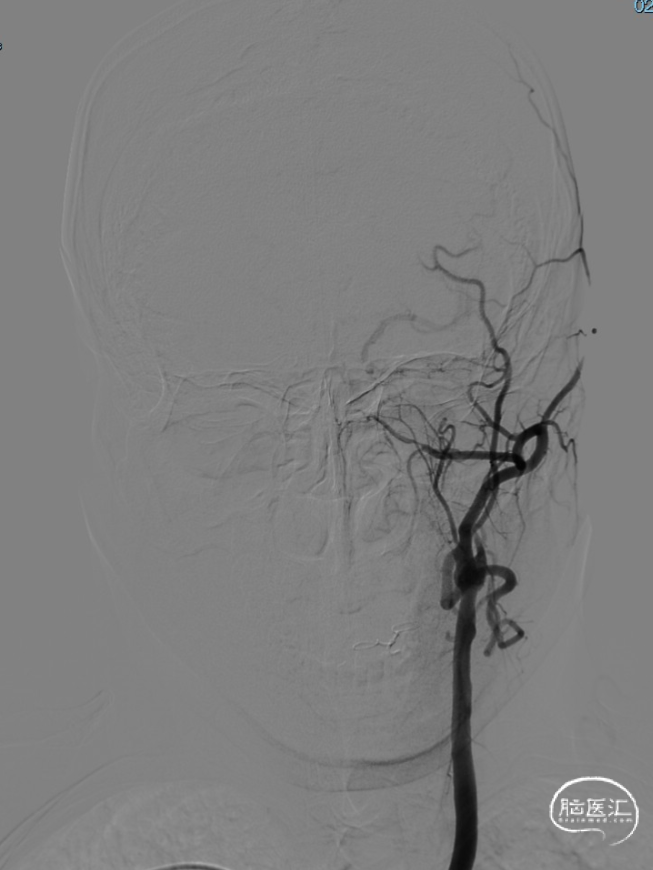

术前DSA造影显示左侧颈内动脉自起始段闭塞,C6眼段以上供血区由颈外动脉眼动脉反向代偿供血,左侧大脑中动脉供血区由前交通动脉代偿供血。

造影后引导下,以0.014in×185cm 微导丝小心通过右侧颈内动脉C1段闭塞处至C3段。随后以0.014in×300cm 微导丝在SL-10微导管支撑下通过闭塞段,成功进入大脑中动脉M1段。

沿微导管送入4.0×30mm Syphonet®取栓支架,于M1-C7段释放作为栓塞保护装置。

沿4.0×30mm Syphonet®取栓支架输送导丝送入3.0×12mm SacSpeed®球囊扩张导管,自C1-C7段分次扩张,每次释压后跟进中间导管至C5段,复查造影显示血流通畅。

造影提示C5-C6段仍有残余狭窄。于是利用SacSpeed®球囊扩张导管收回部分Syphonet®取栓支架,在狭窄处直接扩张。

撤回SacSpeed®球囊扩张导管,复查造影。